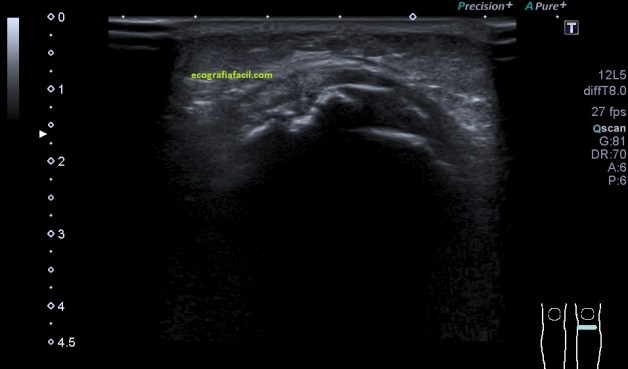

El eje corto presenta este aspecto ecográfico: